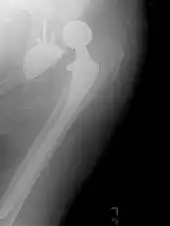

Hemiarthroplasty

Hemiarthroplasty is a surgical procedure that replaces one half of the joint with an artificial surface and leaves the other part unchanged. This class of procedure is most commonly performed on the hip after an intracapsular fracture of the femur neck (hip fracture). The procedure is performed by removing the head of the femur and replacing it with a metal or composite prosthesis. The most commonly used prosthesis designs are the Austin Moore and Thompson prostheses. A composite of metal and high-density polyethylene that forms two interphases (bipolar prosthesis) can be used. The monopolar prosthesis has not been shown to offer any advantage over bipolar designs. The procedure is recommended only for elderly/frail patients, due to their lower life expectancy and activity level. This is because over time the prosthesis tends to loosen or to erode the acetabulum.[100] Independently mobile older adults with hip fractures may benefit from a total hip replacement instead of hemiarthroplasty.[101]

Hip prosthesis for hemiarthroplasty. This example is bipolar, meaning that the head has two separate articulations.